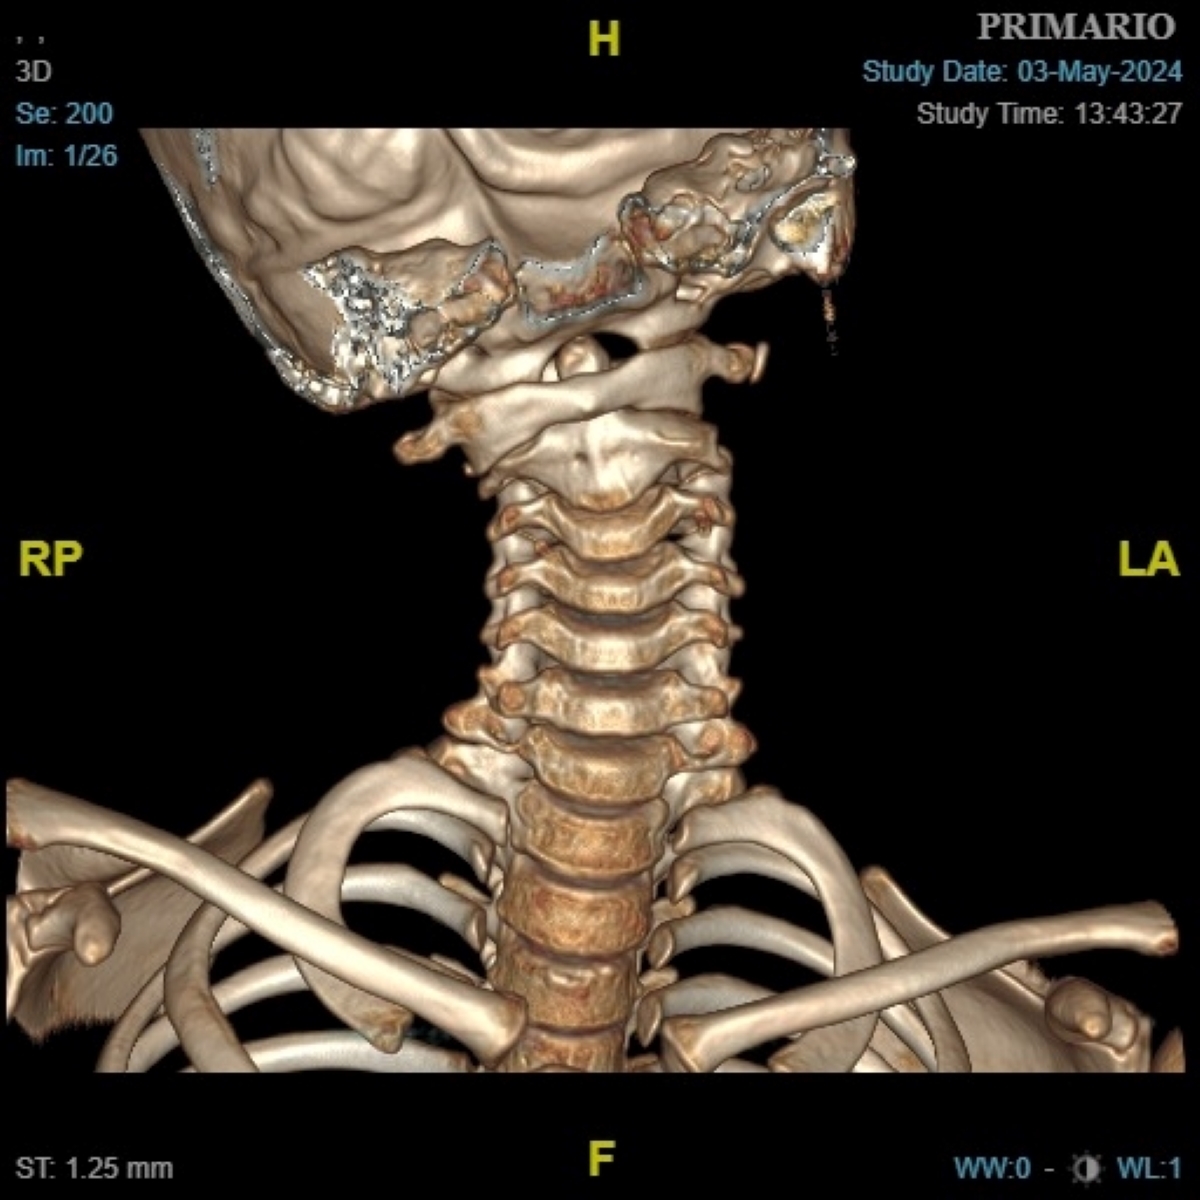

Niña de 9 años de edad, sin antecedentes de interés, que ingresa por cuadro de fiebre, adenitis cervical y tortícolis para la administración de antibioterapia (cefazolina, clindamicina), antiinflamatorios y corticoides i.v. Durante el ingreso presenta desaparición de la fiebre, disminución del tamaño de la adenopatía y mejoría discreta del dolor, pero persiste la tortícolis rígida, por lo que se le realiza una radiografía lateral de faringe, que no es concluyente. Se completa el estudio con TC cervical (Figura 1 y Figura 2).

Figura 2. TC que muestra la reconstrucción coronal 3D con los hallazgos que conducen al diagnóstico.